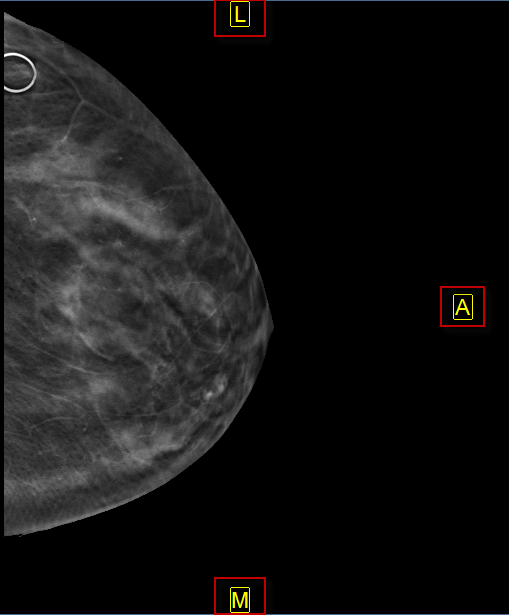

Az alábbi képek egy orrmelléküregi CT-t és egy mammográfiát ábrázolnak, amelyen automatikus orientáció van alkalmazva.

Az automatikus orientáció funkció felülírja a modalitás által meghatározott alapértelmezett betegorientációt, és a felhasználó által meghatározott orientációt alkalmaz. Ha egy képen automatikus orientációt alkalmaznak, a beteg orientációs mutatói kényszerítetten a képen, sárga színnel jelennek meg.

2.  A P/A a szagittális és mammográfiás képek posterior (P) vagy anterior (A) oldalát a képkocka jobb szélére állítja.